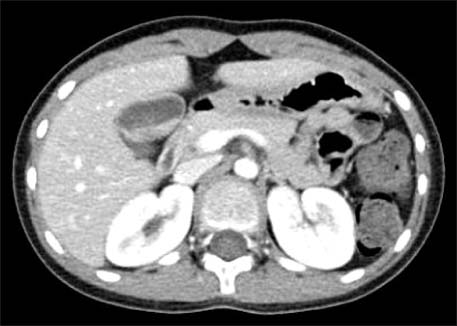

Fig. 1

CT shows multiple gallbladder stones (case 1).

Fig. 1 CT shows multiple gallbladder stones (case 1).